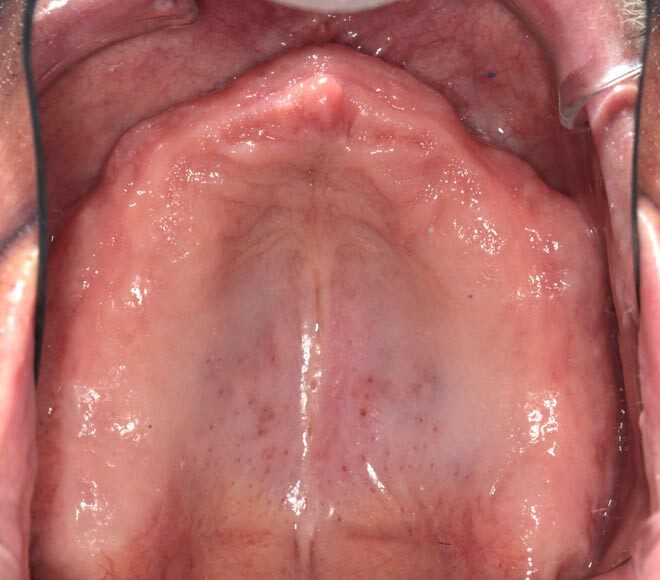

Patient will continue to use his prior upper denture for three months as most of the upper implants were not stable enough for immediate temporary. After 3 months of healing, these implants will be ready for a fixed temporary bridge.

Three months post, first surgery the patient returns for implant uncovering and these are the impression copings preparing for the fixed temporary bridge.